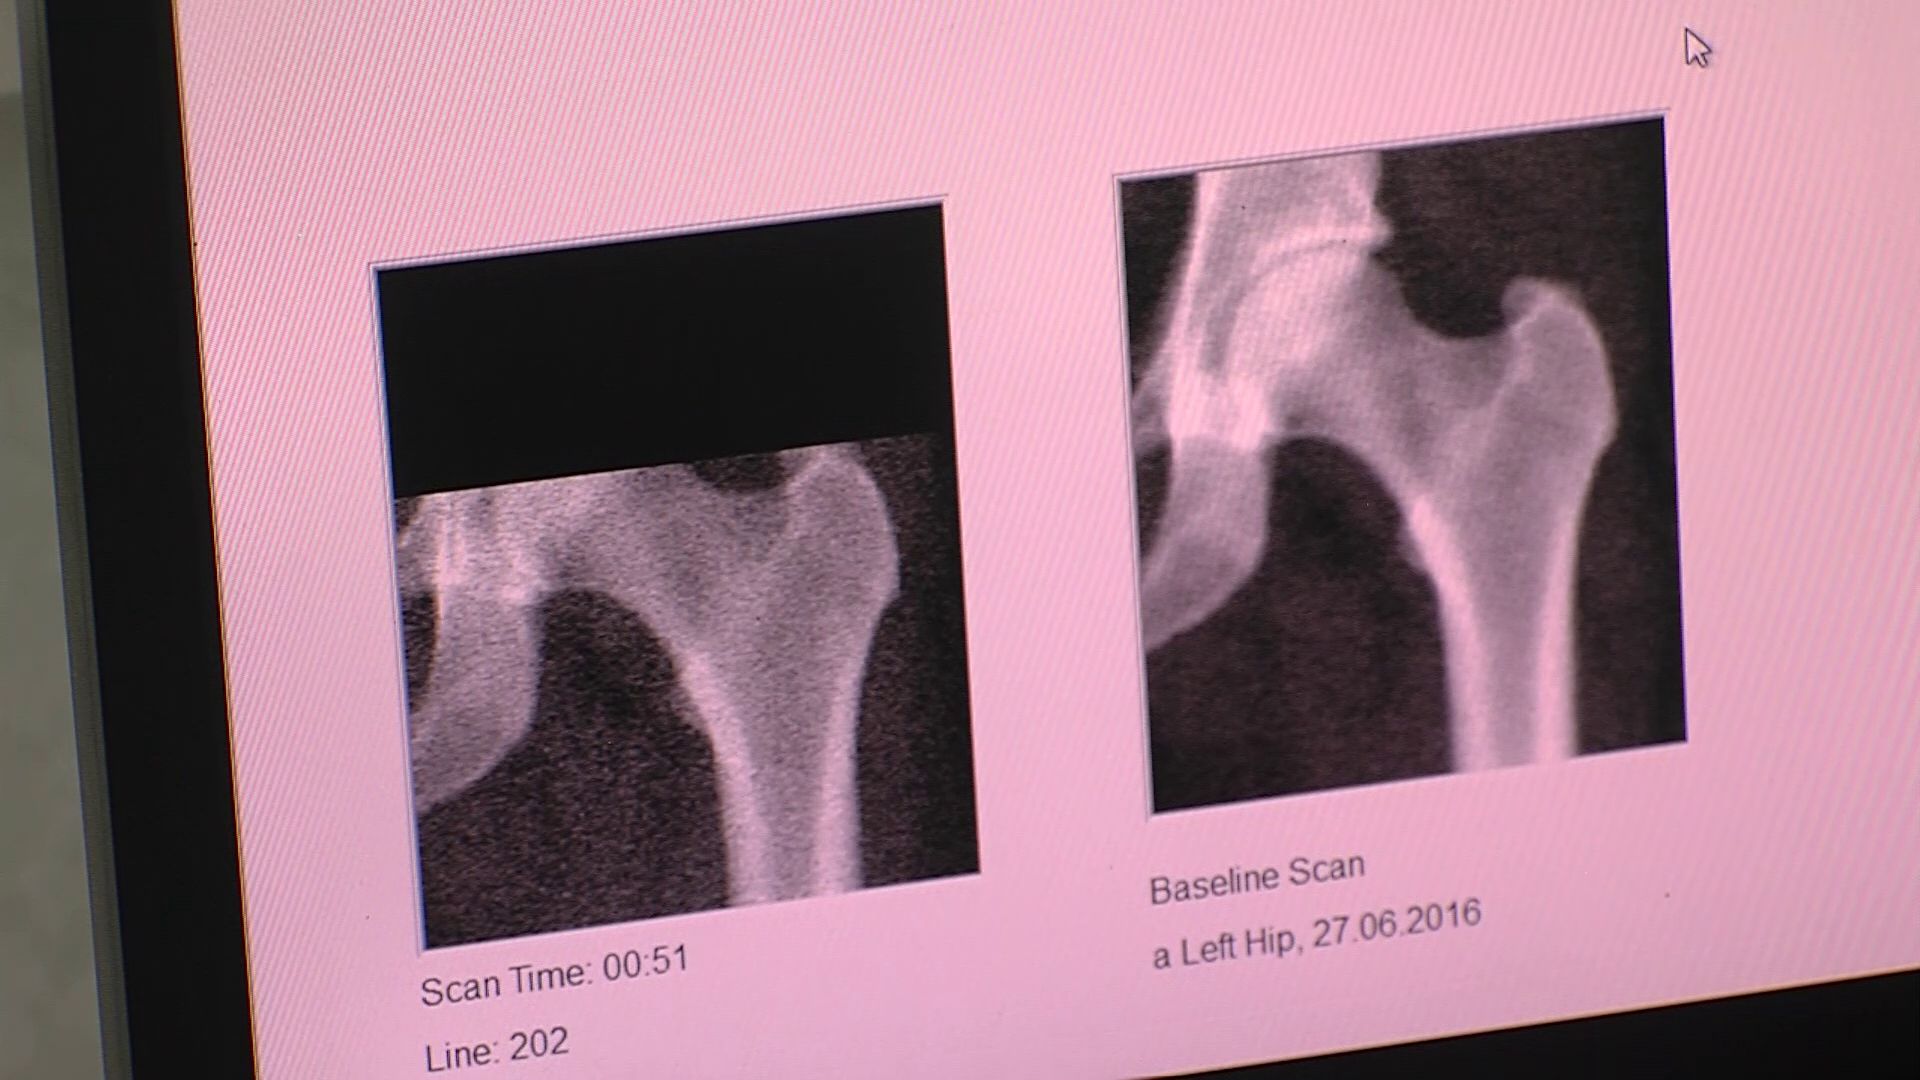

Перед началом обследования в центре остеопороза специалисты измеряют рост и вес пациента, далее проходит обследование на остиоденситометре.

Как сообщают специалисты, остеопороз - широко распространённое заболевание, которое характеризуется снижением плотности и качества костной ткани. А это приводит к снижению физической активности и к переломам. Как правило, остеопороз - заболевание людей старшего возраста. Но профилактику стоит начитать с ранних лет.